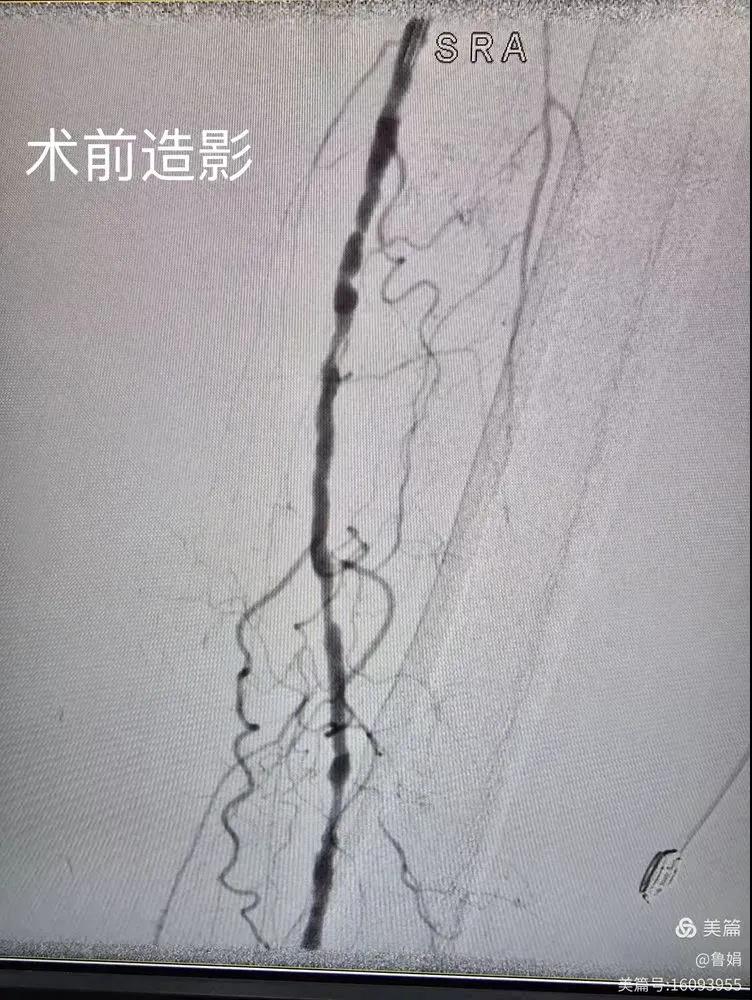

據(jù)悉,該患者,女,73歲,下肢動(dòng)脈硬化閉塞癥,“以靜息痛,間歇性跛行”入院,CTA評估:股淺動(dòng)脈,腘動(dòng)脈間斷性多段重度狹窄,外二科血管外科團(tuán)隊(duì)根據(jù)患者病情,結(jié)合檢查結(jié)果,經(jīng)過科室會(huì)診后,決定對該病人行介入治療。手術(shù)由周創(chuàng)業(yè)副主任與北大一院血管外科專家郭宏杰教授聯(lián)合開展,對股淺動(dòng)脈,腘動(dòng)脈重度閉塞段行血管開通+藥涂球囊擴(kuò)張成形,術(shù)后狹窄明顯緩解,血流恢復(fù)!